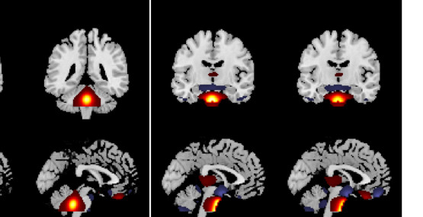

In the last two decades, unsupervised latent variable models---blind source separation (BSS) especially---have enjoyed a strong reputation for the interpretable features they produce. Seldom do these models combine the rich diversity of information available in multiple datasets. Multidatasets, on the other hand, yield joint solutions otherwise unavailable in isolation, with a potential for pivotal insights into complex systems. To take advantage of the complex multidimensional subspace structures that capture underlying modes of shared and unique variability across and within datasets, we present a direct, principled approach to multidataset combination. We design a new method called multidataset independent subspace analysis (MISA) that leverages joint information from multiple heterogeneous datasets in a flexible and synergistic fashion. Methodological innovations exploiting the Kotz distribution for subspace modeling in conjunction with a novel combinatorial optimization for evasion of local minima enable MISA to produce a robust generalization of independent component analysis (ICA), independent vector analysis (IVA), and independent subspace analysis (ISA) in a single unified model. We highlight the utility of MISA for multimodal information fusion, including sample-poor regimes and low signal-to-noise ratio scenarios, promoting novel applications in both unimodal and multimodal brain imaging data.